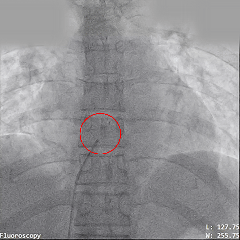

导丝通过ASD固定在肺静脉处

梭形头端可固定在肺静脉处,稳定防脱,建立稳定输送轨道

输送系统通过导丝送至左心房

将PannaWire多功能导丝作为加硬导丝,沿导丝加硬段送入输送鞘系统,导丝提供稳固支撑的同时减少加硬导丝器械交换,提高手术效率